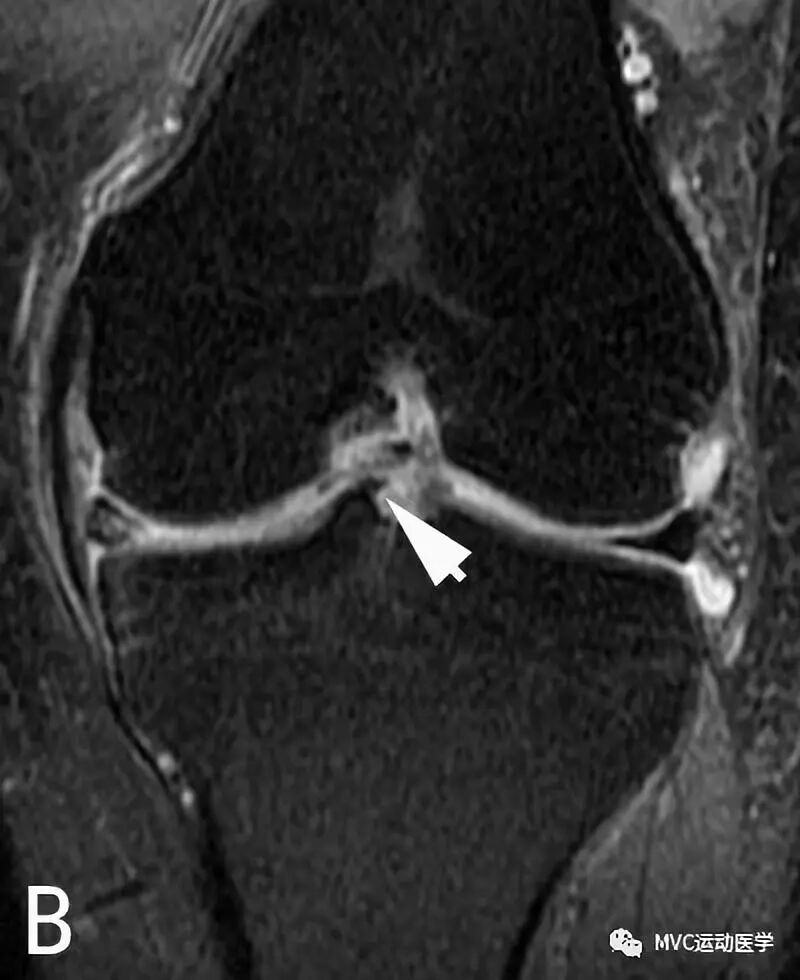

B:冠状位MRI显示腘肌腱(白色箭头)穿过腘肌腱裂孔;

半月板股骨韧带的半月板附着处易与外侧半月板后角的撕裂相混淆。韧带与半月板之间有液体或脂肪填充,可在MRI表现为由前上至后下的斜行撕裂。当膝关节外旋时,半月板股骨韧带与半月板之间的间隙更加明显,Wrisberg束比Humphrey束更易被误认为是半月板撕裂。